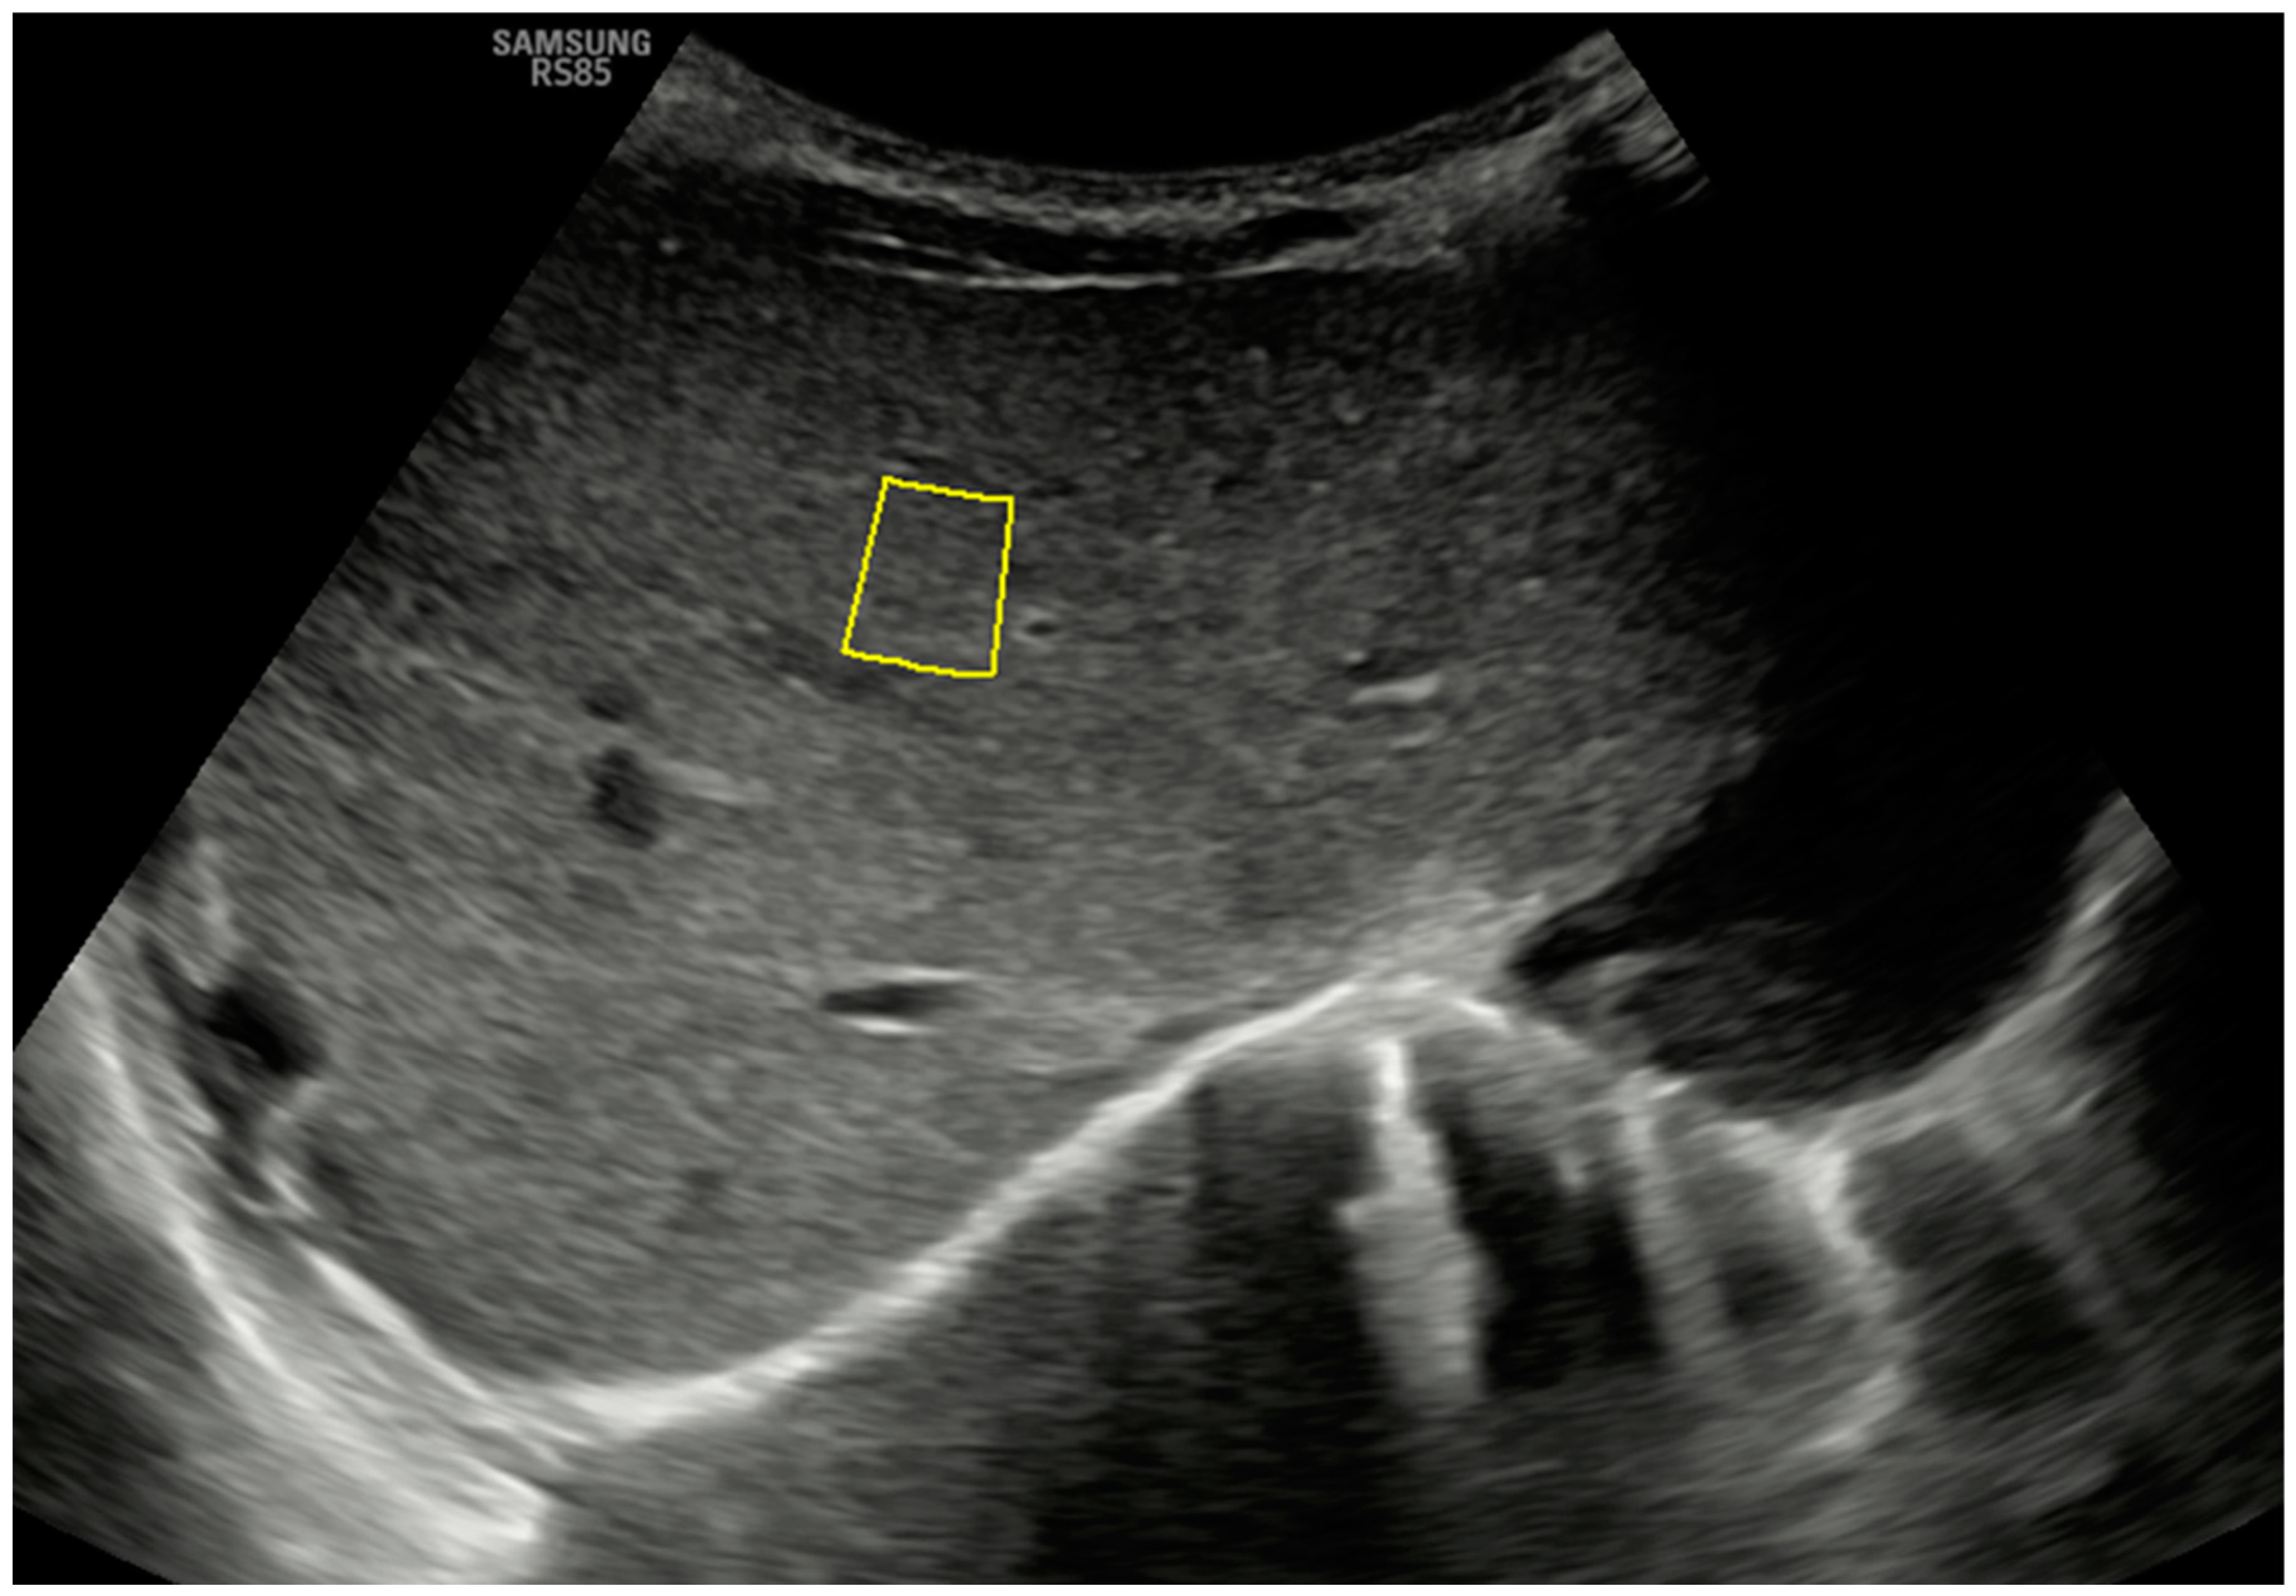

2. Technique